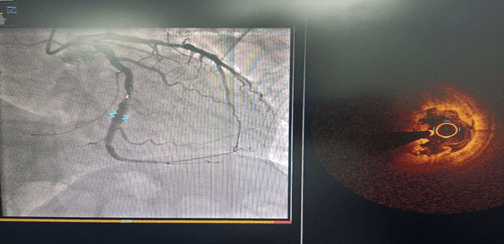

術(shù)前CAG示:左主干閉塞 IABP支持下開通閉塞血管